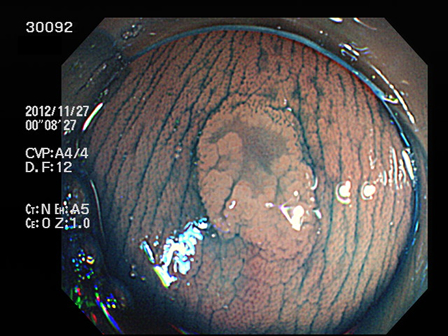

上記100名より抽出した平坦・陥凹型腺腫(=癌化の危険が高いが見落としやすい病変)の内視鏡写真

30001 30005 30008 30014 30016 30019 30020 30022 30023 30024 30025 30026 30027 30028 30029 30031 30033 30034 30036 30038 30044 30045 30047 30049 30051 30053 30055 30056 30057 30058 30059 30060 30066 30069 30072 30073 30074 30076 30077 30078 30079 30080 30081 30082 30083 30084 30085 30087 30088 30092 30097 30098・・・・・・・の52名